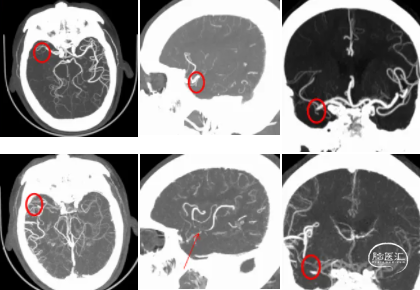

术前影像学检查结果

术前CTA可知责任血管为右侧大脑中动脉,遂在泥鳅导丝及4F多功能管的引导下,直接将8F导引导管送至右侧颈内动脉C1段,造影示右侧大脑中动脉M1远端下干闭塞,同侧大脑前动脉通过脑膜支向大脑中动脉供血区代偿供血,代偿ASTRIN分级2级,将SKATHI远端通路导管送至颈内动脉C4段,随后微导管(Rebar 18)在微导丝(Synchro 14)辅助下,小心通过大脑中动脉下干闭塞段至M2段,再将SKATHI远端通路导管顺利送至大脑中动脉闭塞段近端,并抵住血栓近端,撤出微导丝及微导管,用50ml注射器保持负压吸引抽吸导管,约1分钟后缓慢回撤中间导管至颈内动脉C4段,抽出多枚栓子,复查造影见右侧大脑中动脉各分支完全显影,TICI3级,血流速度正常。

2、多时相CTA可以清楚显示闭塞部位及血管代偿情况,可协助手术路径的判断,为手术决策提供证据。